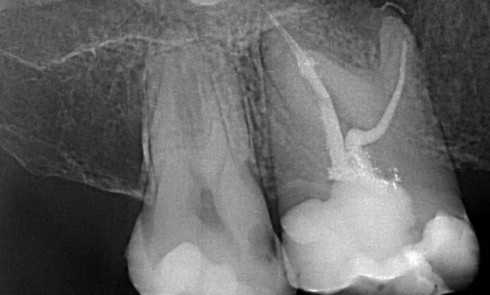

Article réservé à nos abonnés Voyage au centre des canaux : l’endodontie sous l’angle du cone beam

Pour un diagnostic plus précis Lors de la consultation en endodontie, l’interrogatoire et l’examen clinique sont prépondérants dans l’établissement du...